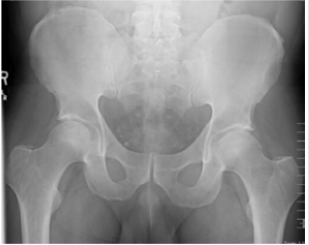

Patient had guarding and pain with movement. Of note, Log roll, FABER and FADIR tests were positive on the right hip. Left hip had slight limitation of movement. Bilateral hip x-rays showed degenerative changes of both hips with subchondral sclerosis with no acute ossific abnormality (Figure 2). MRI imaging of both hips demonstrated AVN without collapse or superimposed fracture or significant effusion or significant marrow edema on the left side (Figure 3). However, intense marrow edema throughout the right femoral head and neck suggested superimposed subcortical fracture on the right side with only minimal deformity of the articular surface. The patient underwent punch biopsy of the left lower extremity purpura; microscopic examination showed numerous extravasated erythrocytes associated with perivascular neutrophils and focal leukocytoclasia in the superficial dermis, consistent with leukocytoclastic vasculitis. Direct immunofluorescence examination was negative for IgM and IgG. However, it showed granular deposition of IgA and C3 within the walls of few superficial dermal vessels. These findings are consistent with IgA Vasculitis. Blood workup included the following: CBC revealed WBC of 7.6 X10E9/L, Hemoglobin of 15.5g/dL, and Platelets of 149 X10E9/L.

The FADIR test, or impingement test, is another abbreviated maneuver for passive complete flexion, adduction, and internal rotation of the leg with the patient supine; a positive test occurs when pain is elicited. The log roll test, also known as passive supine rotation or the Freiberg test, is another specialized physical exam maneuver conducted with the patient supine. During the log roll test, the patient’s leg is extended and relaxed while the clinician internally and externally rotates the leg in a log roll motion. A positive test is when pain or restricted movement of the leg occur [5]. For our patient, the log roll, FABER and FADIR tests were all positive on the right hip. Avascular necrosis can be primary or secondary in etiology. Most common causes of AVN include trauma, glucocorticoid use, and excessive alcohol consumption. The exact pathophysiology of AVN from atraumatic etiology is not yet well understood. However, diagnosis is effective with MRI, the gold standard for AVN diagnosis where sensitivity and specificity reach 99%. MRI remains the imaging modality of choice for early detection and the most effective tool to stage AVN [3]. There are several staging systems for AVN including the Ficat and Arlet Classification System and the Steinberg Staging System. The Ficat and Arlet Classification System is based upon radiographic findings categorized in four stages, with stage I as normal imaging and stage IV as femoral head collapse and osteoarthritis of the hip. According to this system and his imaging, our patient would be categorized as a stage IIA due to the subchondral sclerosis without crescent sign on x-ray.